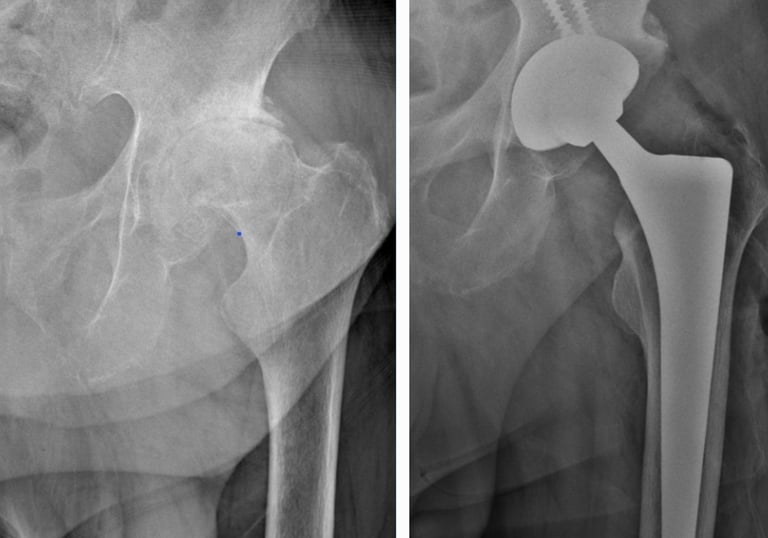

Displasia del desarrollo de cadera: es una alteración en la formación de la articulación de la cadera que está presente desde el nacimiento. Puede provocar que la cabeza del fémur no encaje bien en el acetábulo (la cavidad de la pelvis), lo que con el tiempo ocasiona dolor, cojera y desgaste temprano de la articulación. Su detección y tratamiento oportuno permiten prevenir complicaciones y preservar la función de la cadera.

Secuelas de displasia de cadera